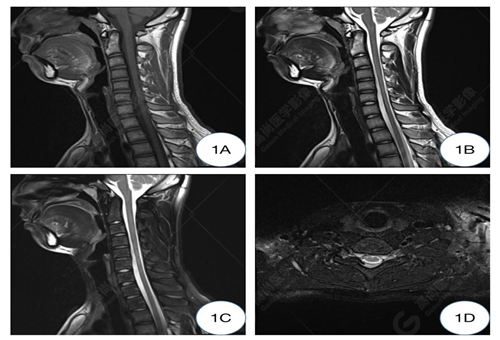

1A-1C圖、常規(guī)仰臥位T1WI及T2WI矢狀位圖示頸椎生理曲度變直,椎體形態(tài)及信號(hào)均正常,椎間隙正常,椎管未見(jiàn)狹窄;1D圖、常規(guī)仰臥位T2WI橫軸位示C5-6水平硬膜外間隙未見(jiàn)增寬,相應(yīng)水平頸髓未見(jiàn)受壓。

C5-6椎體水平頸髓及曲頸位頸椎異常改變,可符合平山病表現(xiàn)。

影像學(xué)常規(guī)中立位可表現(xiàn)為下頸椎和頸背交界處的脊髓萎縮變平,神經(jīng)膠質(zhì)增生區(qū)域在T2WI序列顯示為高信號(hào),有時(shí)僅表現(xiàn)出可疑征象,需補(bǔ)充屈曲位掃描。HD 在屈曲 MRI 上具有特征性的成像特征。屈曲位MRI顯示,低位的頸髓向前移位,受壓變扁平,可合并萎縮,后部的硬腦膜向前移位,后硬膜外間隙增寬,形成新月形區(qū)域,并有異常信號(hào)改變及流空血管影,增強(qiáng)掃描硬膜外異常信號(hào)常呈明顯強(qiáng)化,提示其為充血的后靜脈叢可能,因?yàn)槠湓谥辛⑽粧呙钑r(shí)完全消失。